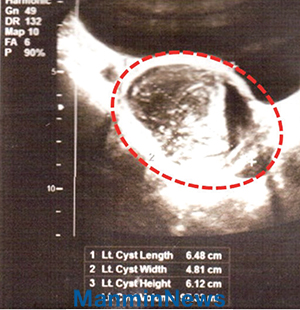

óÀ½¿¡´Â ±×³É Âü°í ³Ñ°å´Âµ¥, ÀÏÁÖÀÏ µÚ ´Ù½Ã ¾ÆÇÁ°í ÅëÁõÀÌ Àüº¸´Ù ´õ¿í ½ÉÇØÁ® ºñ¸íÀ» Áö¸£¸ç ¹Ù´Ú¿¡ ³ªµß±¼¾úÁö¿ä. Àú´Â ÇÒ¸Ó´ÏÀÇ ¿¬¶ôÀ» ¹ÞÀº ¾ÓÈå¹Ù¾ß¸£ ¼±±³»ç´ÔÀÇ µµ¿òÀ¸·Î º´¿ø¿¡ °¬½À´Ï´Ù. ÃÊÀ½ÆÄ »çÁø ÃÔ¿µ °á°ú, ¿ÞÂÊ ÀڱñÙÁ¾À̾úÁö¿ä. ÀÇ»ç´Â ¶Ù¸é ¾È µÇ°í ¿ÊÀ» µû¶æÇÏ°Ô ÀÔ¾î ÁÖ¾î¾ß ÇÑ´Ù°í Çß°í, ¼ö¼úÀ» ¹ÞÁö ¾ÊÀ¸¸é ±ÙÁ¾ÀÌ ´õ Ä¿Áö°í ÅëÁõÀÌ ´õ ½ÉÇØÁö´Ï±î »¡¸® ¼ö¼úÀ» ÇØ¾ß ÇÑ´Ù°í ¸»Çß½À´Ï´Ù.

ÃÊÀ½ÆÄ »çÁø

±âµµ¹Þ±â Àü: Àڱÿ¡ 6x5cmÀÇ È¤ÀÌ º¸ÀÓ

Áø·á ±â·ÏÁö

±âµµ¹ÞÀº ÈÄ: ȤÀÌ »ç¶óÁö°í Á¤»óÀÓ